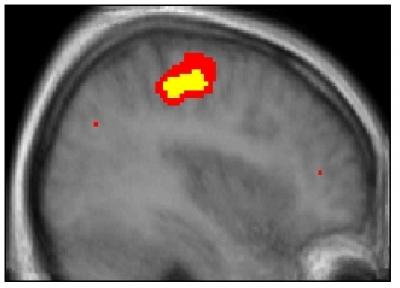

Players were able to learn from their own successful selections but those of their competitor failed completely to increase their neural activity. Instead, it was their competitor's unexpected failures that generated this additional brain activity. Such failures generated both reward signals in the brains of the players, and learning signals in regions involved with inhibiting response. This suggests that we benefit from our competitors' failures by learning to inhibit the actions that lead to them.

Surprisingly, when players were observing their competitor make selections, the players' brains were activated as if they were performing these actions themselves. Such 'mirror neuron' activities occur when we observe the actions of other humans but here the players knew their opponent was just a computer and no animated graphics were used. Previously, it has been suggested that the mirror neuron system supports a type of unconscious mind-reading that helps us, for example, judge others' intentions.